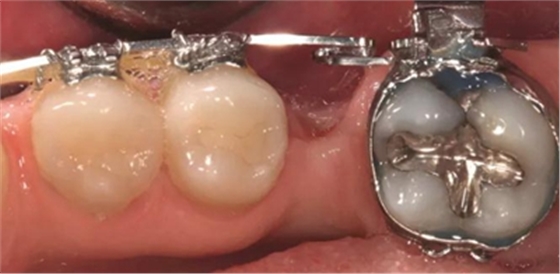

圖2d. 3個(gè)月后,獲得顯著的骨增量,同時(shí)創(chuàng)造出1.6mm的近遠(yuǎn)中修復(fù)空間

圖5g. 3 個(gè)月后完成了位點(diǎn)加速改建,近遠(yuǎn)中向的修復(fù)空間和頰舌向的骨增量均增加

術(shù)后3個(gè)月,右側(cè)第一磨牙的空間約為9mm(3個(gè)月中增加了1.6mm),逐漸接近了對(duì)側(cè)第一磨牙的空間(也約9mm)(圖6a)。術(shù)后7個(gè)月的錐束CT顯示,右側(cè)第一磨牙區(qū)域獲得了2.5mm的水平骨增量(圖6b 和c)。左側(cè)第一磨牙的無(wú)牙區(qū)保持相同的尺寸,在種植體植入前也需要骨增量。